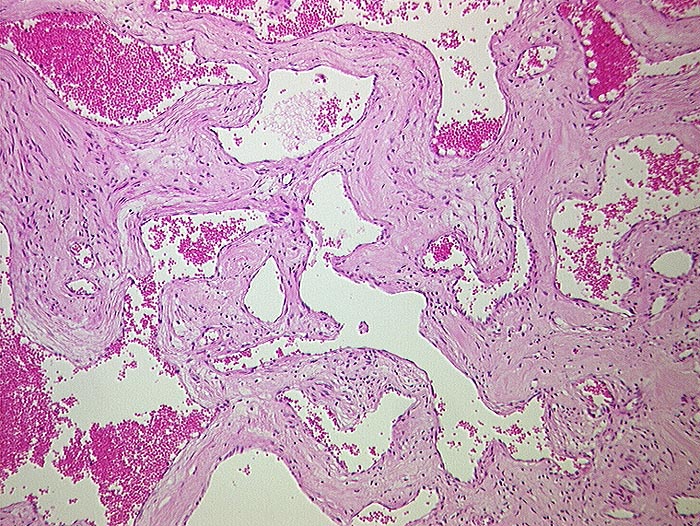

PathoPic ID 898 - Kavernöses Hämangiom

Kavernöses Hämangiom

benigner Tumor

Leber

Tumor aufgebaut aus ektatischen Gefässen.

Tumordurchmesser 10cm.

Histologie